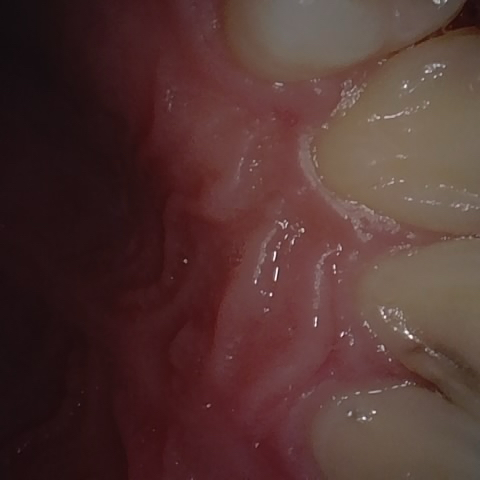

Annotated as "Good"